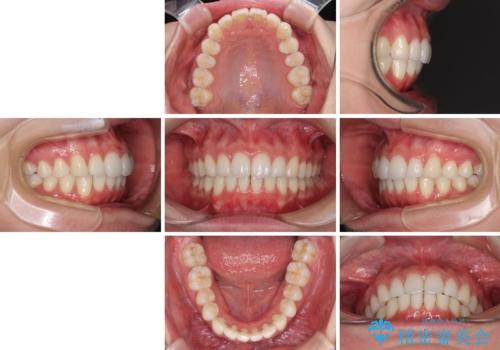

- 上下前歯の叢生を気にして来院された患者様です。

以前矯正をした後戻りということで、歯列不正はそれほど大きくなかったため、インビザライン・ライトを用いて矯正治療を行うこととしました。

インビザラインは1日に22時間を目安に装着していただきますが、装着時間が十分でないとシミュレーション通りに動かないことがあります。

前歯のデコボコが残っており、シミュレーション通りに動いていない部分がありましたが、再矯正であることやご本人の満足いくところまでデコボコが改善されたとのことで、治療を終了することとしました。